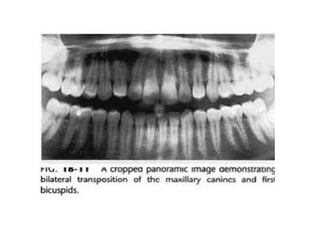

5. Transposition

Merupakan kondisi dimana dua gigi yang

bersebelahan berubah posisi pada dental arch.